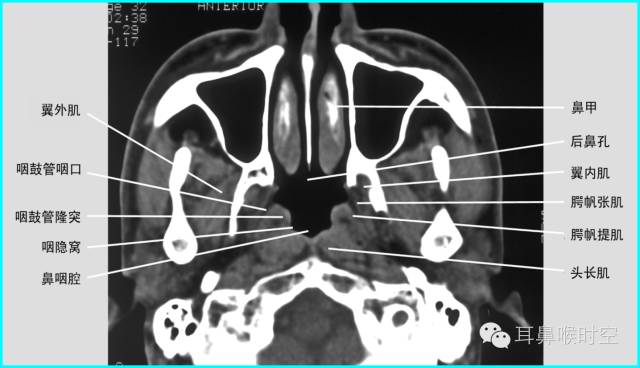

C T— computed tomography

咽部正常CT表现

(1)鼻咽腔层面:

CT检查扫描方法

①鼻咽部轴扫:常规OML (听眦线)

扫描体位:标准仰卧头颅正位

扫描参数:OML基线,层厚3mm/5mm,螺距1.0。

扫描范围:以侧位作为定位线,包括中耳乳突进行螺旋方式扫描

部分进行静脉增强扫描;

②冠状位扫描:以蝶-枕骨结合面为基点

CT 观察与测量方法

①标准CT 轴位:主要观察12项结构

鼻咽腔的形态

腺样体大小与形态

咽隐窝

咽鼓管咽口

圆枕

鼻后孔的阻塞情况

翼内外板

翼内外肌

咽旁间隙

邻近骨质有无破坏

鼻旁窦

中耳乳突等。